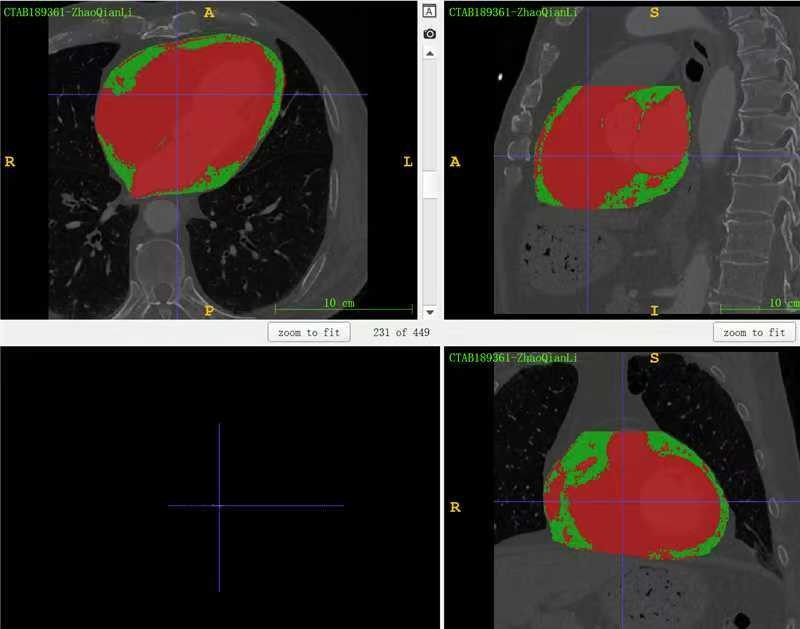

一共460例,由3名分别具有1年、5年、25年胸部放射诊断经验的住院医师、主任医师将每例患者的CCTA图像导入至 3D Slicer 5.2.0 软件,分别通过半自动方法,逐层勾画心包轮廓并通过-200HU~30HU范围阈值分割出CCTA全部脂肪密度区域,应用布尔运算提取出心包轮廓内的脂肪组织,医师人工复核确认心包脂肪区域轮廓符合客观情况;在心包边界不清的位置,以肺门胸膜反折、左心房后壁等结构作为参考,对于因成像时图像重建过滤器不同而导致的标准差过高的病例,阈值分割后增加人工复核一次,将心肌、血管等结构排除出勾画区域。在上述统一标准下完成勾画任务,勾画完成后,将原始CCTA和掩膜分别保存为三维NIfTI格式文件。为了减少勾画任务的信息偏倚干扰,3名参与勾画任务的医师事先均不告知研究目的、各CCTA病例患者的相关临床资料。